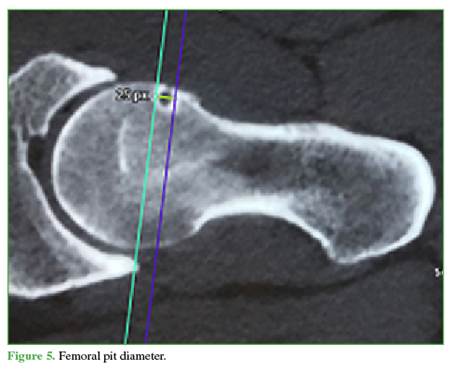

SP morphology: The following parameters were analyzed on axial oblique CT or arthro-MRI slices: 1) measured by a tangent from the anterior femoral cortex to the deepest point of the SP (Figure 4); 2) measured by a tangent from the proximal femoral border to the most distal point of the SP (Figure 5); 3) Shape: round, oval, or multilobulated; and 4) Rim: complete (cyst) or incomplete (notched).

The mean distance from the SP to the femoral head center was 12.5 mm (range, 6–28); mean depth 6.3 mm (range, 2–14); and mean diameter 6 mm (range, 2–12). Eighty-two point one percent of SPs had complete rims, and 17.9% incomplete rims. The shape was round in 78.6% (22 cases), oval in 10.7% (3 cases), and multilobulated in 10.7% (3 cases).